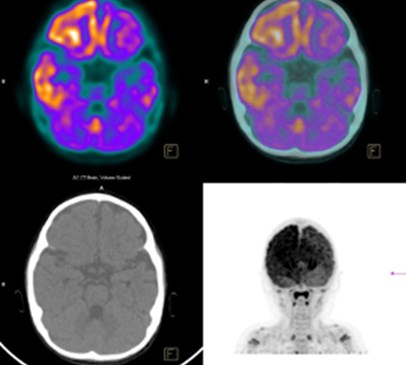

This four-year study involving 126 patients from across Europe compared two functional imaging techniques, PET and functional MRI (fMRI), with a well-established test, the Coma Recovery Scale-Revised (CRS-R)

This four-year study involving 126 patients from across Europe compared two functional imaging techniques, PET and functional MRI (fMRI), with a well-established test, the Coma Recovery Scale-Revised (CRS-R). It demonstrated that repeated testing with CRS-R and a PET scan using a specific imaging agent was about 74% accurate in predicting the extent of recovery within a year, compared with 56% for fMRI.

During the study, the PET scanning technique showed brain activity consistent with some level of consciousness in a third of the 36 patients who were diagnosed as unresponsive on the CRS-R test. This led the authors to conclude that CRS-R alone is not a reliable way of assessing consciousness, and supplementing it with this PET scan can lead to much more accurate results.